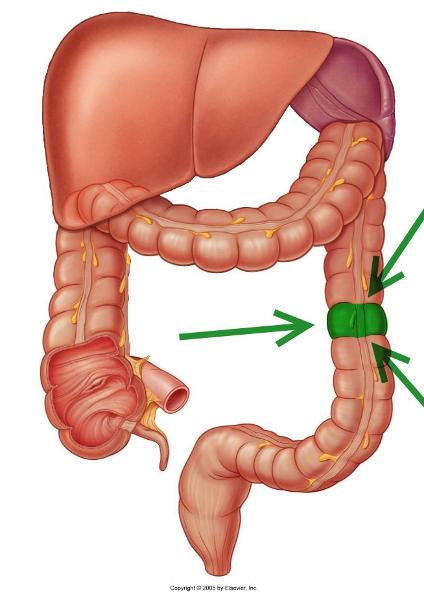

Ascending/transverse/descending/sigmoid colon

Cecum

Haustra

Ileocecal valve

Ileum

Jejunum

arrow

Rectum

Taeniae coli

Vermiform appendix